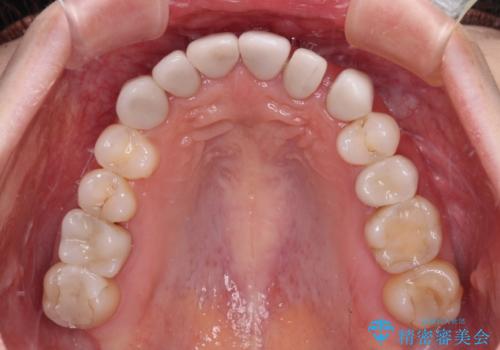

- 上下前歯のデコボコと奥歯の欠損を気にして来院された患者様です。

右下の欠損分は奥歯が倒れ込んでスペースがなくなっていたため、矯正治療により本来の位置に歯を移動させ、オールセラミックブリッジによる欠損補綴治療を行うこととしました。

全顎的にセラミッククラウンが多く装着されているため、インビザラインによる矯正治療を行うこととしました。

右下は移動量が多いため、十分な移動が達成されない場合はワイヤー装置を使用する予定としておりましたが、しっかりとマウスピースを装着してくださったため、前歯とともに十分に歯を動かすことができました。